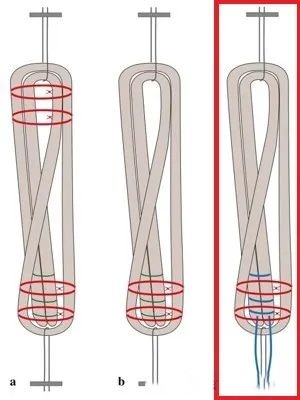

在ACL全内重建术中,对于移植物的编织方法也有很高的技术要求。于传统肌腱的简单编织缝合不同,由于全内移植物两端均使用悬吊固定,因此需要采用埋结编织法,但笔者更喜欢一种杂交改良的埋结编织法(Raul Mayr, KSSTA)。

上述的C法就是作者改良的埋结编织缝合法

测试表明,这种方法不仅缝合速度超快,而且生物力学超强